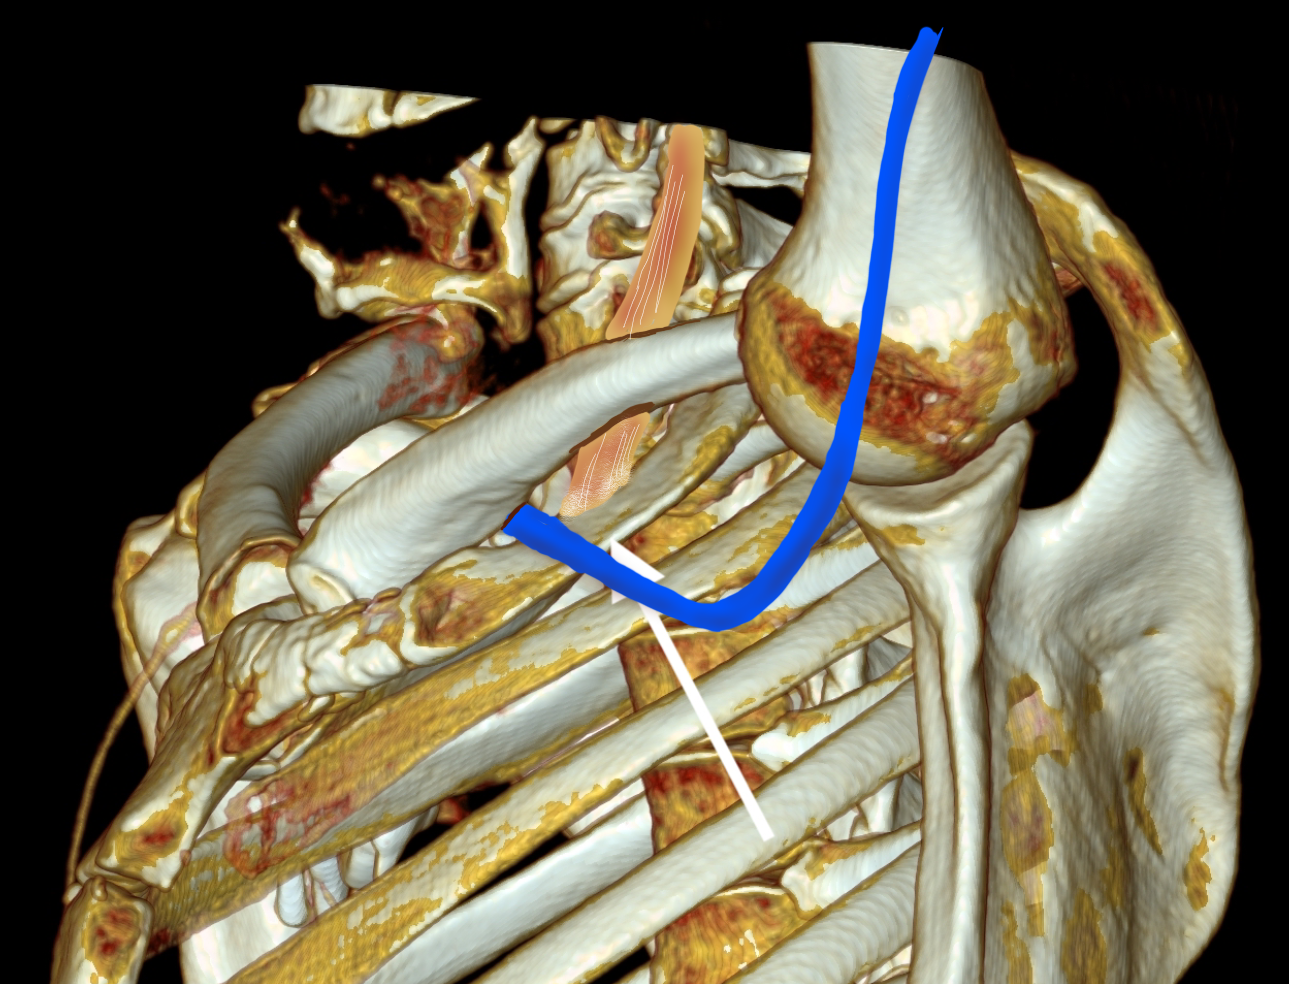

The patient’s first reaction was a dubious expression. After all, in this day and age, isn’t it barbaric to offer to cut out a rib? Why not put a stent there? A CT venogram was obtained showing the subclavian vein occlusion, but we knew that. I use the 3D surface reconstructions extensively as a visual map to determine surgical approach. I remove first ribs through both supraclavicular and transaxillary approaches, choosing one or the other.

The 3D reconstruction of the bones showed that to get to the first rib section underlying the vein, it was best approached via a transaxillary approach. The arrow in the image shows the flare in the first rib where the anterior scalene muscle attaches. Adding muscle shows that in this well muscled patient, getting to the first rib would be a challenge -for the people holding the retractors.